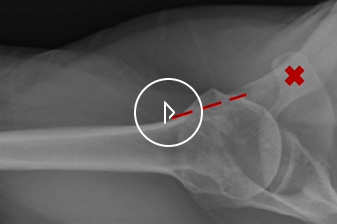

• ultrsound

for Rotator Cuff Tear Diagnosis

Musculoskeletal ultrasound is an injury assessment technique that uses sound waves to create images of painful or injured soft tissues in the extremities.